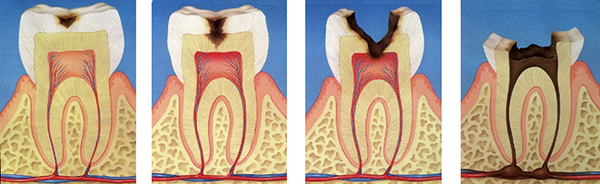

In "dental caries, "mutans bacteria adhere on the tooth surface and produce acid from sugar.

This causes the teeth to dissolve and cold or hot foods begin to sting.

If the tooth becomes severely decayed, it can reach the pulp inside the tooth, causing pain even when you're not doing anything.

Bacteria that have reached the pulp will travel through the root canal, the cavity where the pulp used to be, to the the root apex, and finally proliferate in the bone that supports the tooth (Fig. 8).